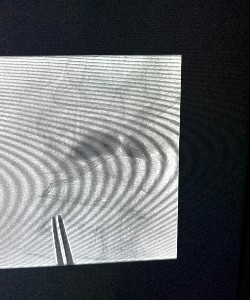

Background to electrochemical measurement approach. The critical measurement approach that enables simultaneous electrochemical detection of dopamine, serotonin, and norepinephrine is an electrochemical method called “fast scan cyclic voltammetry”. This approach has been utilized in rodents and rodent brain tissue for over 25 years. Briefly, a voltage is applied to a carbon fiber microelectrode. If this voltage is greater than or equal to the oxidation potential of a chemical species, then an electrochemical oxidation reaction takes place and the transfer of electrons (to the carbon fiber) is measured as a change in current. By quickly scanning over a range of applied potentials (e.g., -0.6V to +1.4V and back to -0.6V at a scan rate of 400V/s), a range of electrochemical currents can be detected. We have developed a machine learning based algorithm that allows us to infer the chemical species’ identity and concentration from this induced electrochemical spectrum. Tests like those shown in Figure 3 demonstrate that we can continuously monitor dopamine, serotonin, and norepinephrine micro-fluctuations with 100ms temporal resolution, which is orders of magnitude faster and with direct chemical specificity better that existing non-invasive measurement modalities like fMRI and PET and invasive approaches like microdialysis.